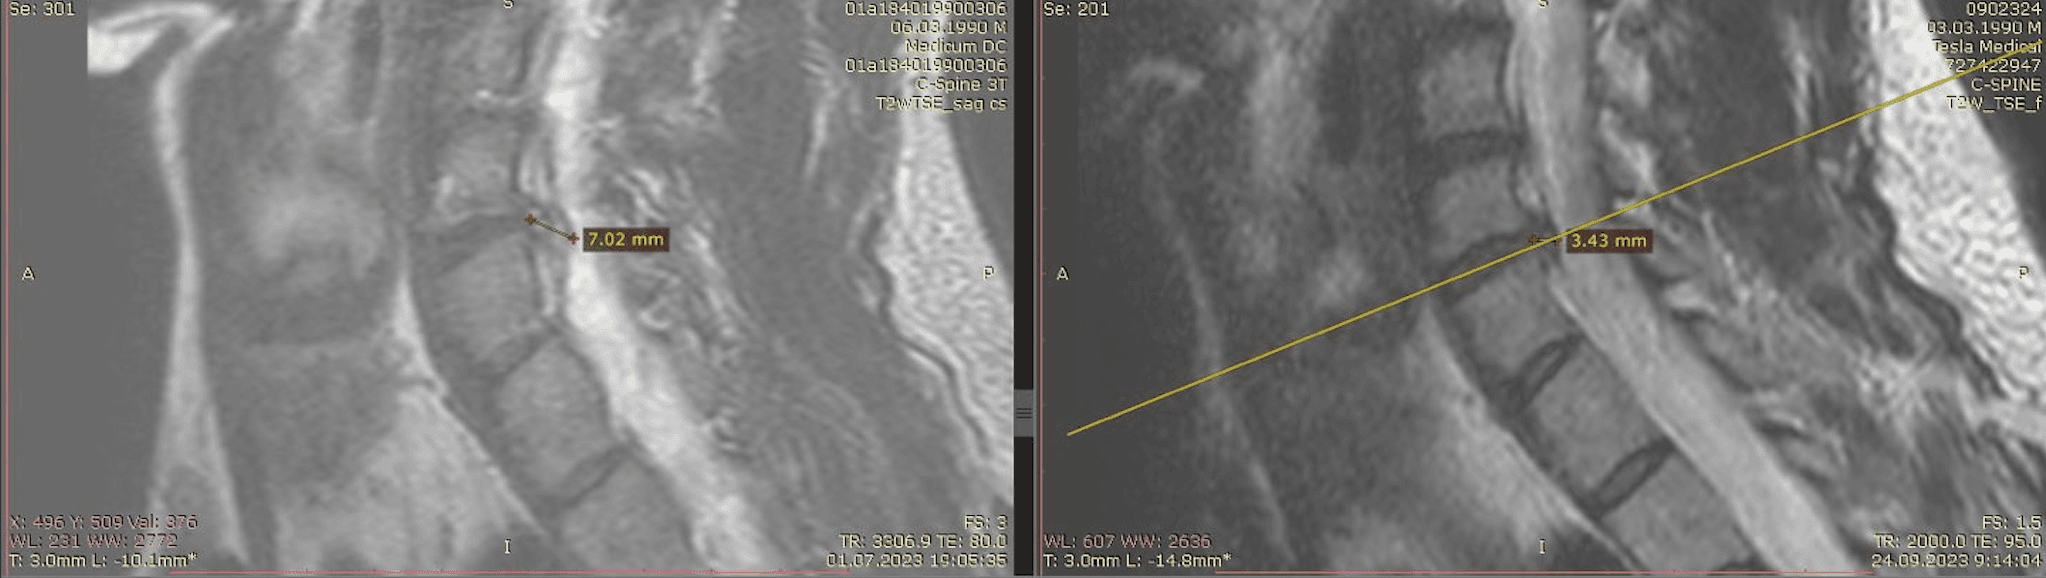

Метод лікування грижі шляхом стимуляції резорбції в Україні був впроваджений у 2020-2021 роках.  Алгоритм оцінки грижі на предмет резорбції, що використовується у клініках – є авторським, розроблений лікарем Боханом А.Ю.